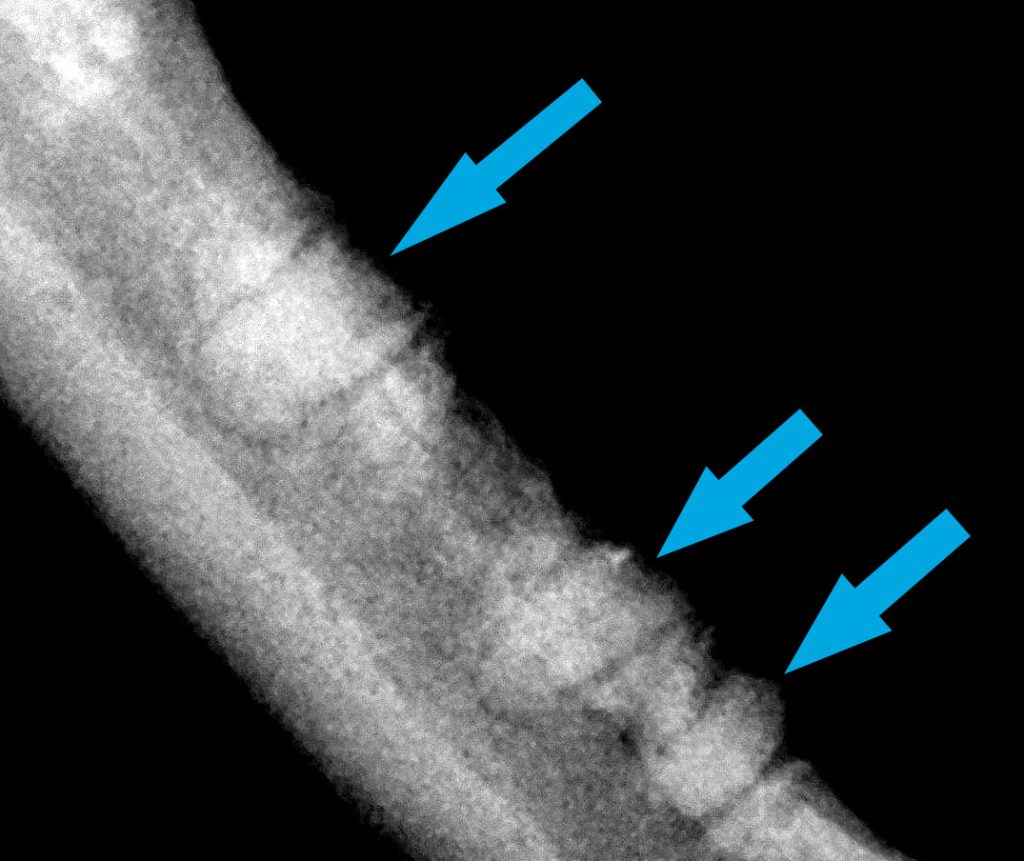

ESTUDIO RADIOLÓGICO DENTAL

El estudio radiológico dental correspondiente desveló la presencia de restos radiculares de los dientes 207 302, 308, 404, 408, 409 (incisivo, premolares y colmillo).

-Al ser la GECF una enfermedad idiopática de origen inmunomediado es imprescindible que no queden restos radiculares en la cirugía de exodoncias para evitar así el estímulo antigénico que mantenga la inflamación y el dolor en el paciente.

-Dado el escaso tamaño de los dientes del gato, sin la técnica ni el equipamiento adecuado, es relativamente sencillo dejar algún resto radicular (en ocasiones de forma desapercibida). El fresado «a ciegas» de un posible resto radicular, además de que está contraindicado por sus posibles complicaciones asociadas, no soluciona el problema de que queden restos radiculares.